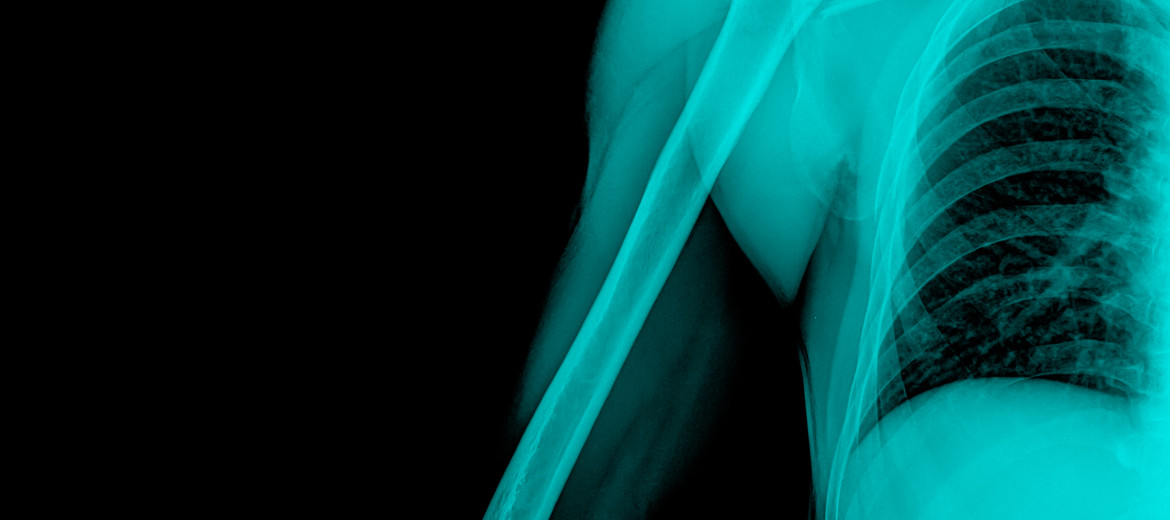

Hackettstown – The Orthopedic Institute of New Jersey has expanded its services with the addition of the Orthopedic Institute of New Jersey Bone Health Center. The director of this division of the Practice is Dr. Jason Wu, Board Certified Rheumatologist. Dr. Wu explains the need for this component of the Practice by indicating that “bone loss can occur over many years. The result of this may only manifest itself when an individual suffers a fracture or notices a loss in height. There are steps that can be taken to keep bones strong. Our goal is to educate, diagnose and treat patients with brittle bones and to prevent fractures.” The Center utilizes a multi-disciplinary approach in treating patients, taking advantage of the Orthopedic, Pain Management, Spinal Care and Physical Therapy professionals at the Practice to best assist patients. The Services offered within the Center include:

According to the National Osteoporosis Foundation, millions of Americans – 52 million to be exact – have low bone density or osteoporosis. In fact, about one in two women and up to one in four men over the age of 50 will break a bone due to osteoporosis. By 2020, half of all Americans over age 50 are expected to have low bone density or osteoporosis. There are no symptoms in the early stages of osteoporosis. Individuals who fall within the following categories may find the Center to be of particular value: